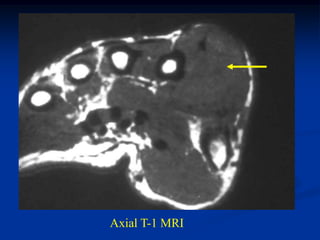

CLASSIC Case #123

12 year female with chondroblastoma proximal tibia

Coronal post gad MRI

Sagittal T-2 MRI